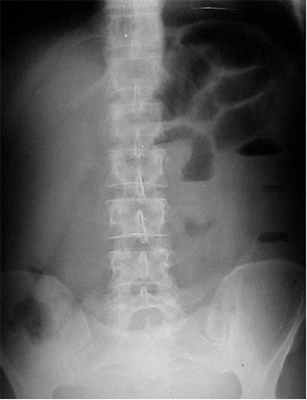

- Симптом перистости (поперечная исчерченность в форме растянутой пружины) встречается при высокой кишечной непроходимости и связан с растяжением тощей кишки, имеющей высокие циркулярные складки слизистой. Контрастное исследование желудочно-кишечного тракта применяется при затруднениях в диагностике кишечной непроходимости. Больному дают выпить 50 мл бариевой взвеси и проводят динамическое исследование пассажа бария. Задержка его до 4-6 часов и более дает основание заподозрить нарушение двигательной функции кишечника.

Отличить паралитическую непроходимость кишечника от механической тонкокишечной непроходимости с помощью обзорной рентгеноскопии бывает довольно сложно (см. таблицу). Рентгеноконтрастное исследование применяется с целью дифференциальной диагностики КН в сложных случаях [2, 7, 10, 13]. Вариант введения контраста зависит от предполагаемого уровня окклюзии кишечника. Так, бариевую взвесь внутрь дают при признаках высокой обтурационной непроходимости и с помощью клизм вводят при симптомах низкой непроходимости. При необходимости динамического исследования пассажа бария внутрь назначают рентгеноконтрастный препарат, при задержке которого более 6 ч в желудке и 12 ч в тонкой кишке диагностируется нарушение проходимости или двигательной активности кишечника. При механической непроходимости контрастная масса ниже препятствия не поступает.

Условия проведения исследований с контрастным веществом при ОКН:

1) рентгеноконтрастное исследование для диагностики ОКН можно использовать лишь при полной убежденности (на основании клинических данных и результатов обзорной рентгенографии брюшной полости) в отсутствии странгуляционной формы непроходимости, составляющей угрозу быстрой утраты жизнеспособности ущемленной петли кишки;

2) динамическое наблюдение за продвижением контрастной массы необходимо сочетать с клиническим наблюдением, в ходе которого фиксируются изменения местных физикальных данных и общего состояния больного. В случае усугубления местных признаков непроходимости или появления признаков эндотоксикоза вопрос о неотложном оперативном вмешательстве должен обсуждаться независимо от рентгенологических данных, характеризующих продвижение контраста по кишечнику;

3) если принимается решение о динамическом наблюдении за больным с контролем за пассажем по кишечнику контрастной массы (проба Шварца), то такое наблюдение следует сочетать с проведением лечебных мероприятий, направленных на устранение динамического компонента непроходимости. Эти мероприятия заключаются, главным образом, в применении антихолинергических, антихолинэстеразных и ганглиоблокирующих средств, а также проводниковой (паранефральной, сакроспинальной) или перидуральной блокады [1-3, 7, 9-12].